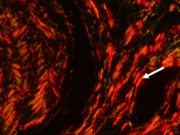

Carcinoma epitelial/mioepitelial. Colágeno Tipo I (flecha). Picrosirius red. Microscopía de polarización

Carcinoma adenoide quístico. Colágeno Tipo I (flecha). Picrosirius red. Microscopía de polarización

El estroma juega un rol importante en los procesos tumorales de invasión y metástasis. Las fibras de colágeno tipo I son el principal componente estructural del estroma en distintos tumores. Sin embargo, hay muy pocos estudios en los tumores de glándulas salivales. Basándonos en estos antecedentes el objetivo de la presente comunicación fue estudiar las características del colágeno con Picrosirius red/polarización en tumores benignos y malignos de glándulas salivales para evaluar su posible rol en los mecanismos de progresión tumoral. Cortes histológicos de adenoma pleomórfico, carcinoma adenoide quístico y carcinoma epitelial mioepitelial se colorearon con H/E y Picrosirius red y se examinaron con microscopio de polarización. La birrefringencia del colágeno con Picrosirius/polarización resultó diferente en el estroma de los tumores malignos (carcinoma adenoide quístico y carcinoma epitelial mioepitelial), con predominio de colágeno I, en comparación con el tumor benigno (adenoma pleomórfico), con predominio de colágeno III. El diferente perfil de coloración en las fibras colágenas producidas en el estroma de los tumores analizados podría relacionarse con diferentes mecanismos de expansión tumoral, los que fueron poco estudiados en los tumores de glándulas salivales. Más estudios son necesarios para obtener resultados más concluyentes que contribuyan al diagnóstico, pronóstico y tratamiento.